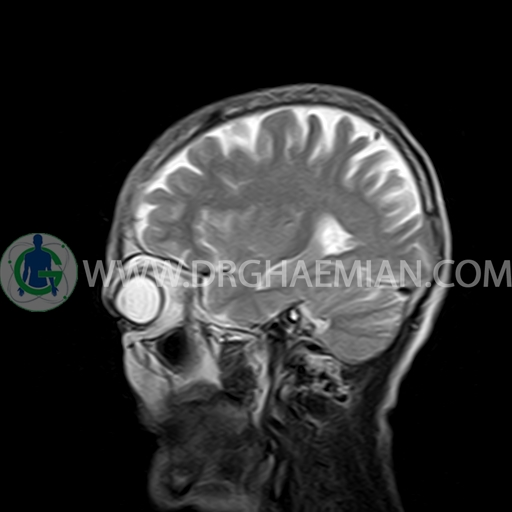

ام آر آی مغز با استفاده آهنربا های قوی و امواج رادیویی تصاویری از مغز و بافت های عصبی پیرامونی آن ایجاد می کند. در این کیس مننژیوم به همراه هیپراستوز استخوانی سمت چپ دیده می شود.

a well – defined dural based mass lesion ( 27x55mm ) in left parietal region with signal change in adajacent bone suggestive for meningioma with bone hyperosteosis

mass effect & edema in left parietal lobe

are seen

COMMENT : MRI with contrast is recommended .